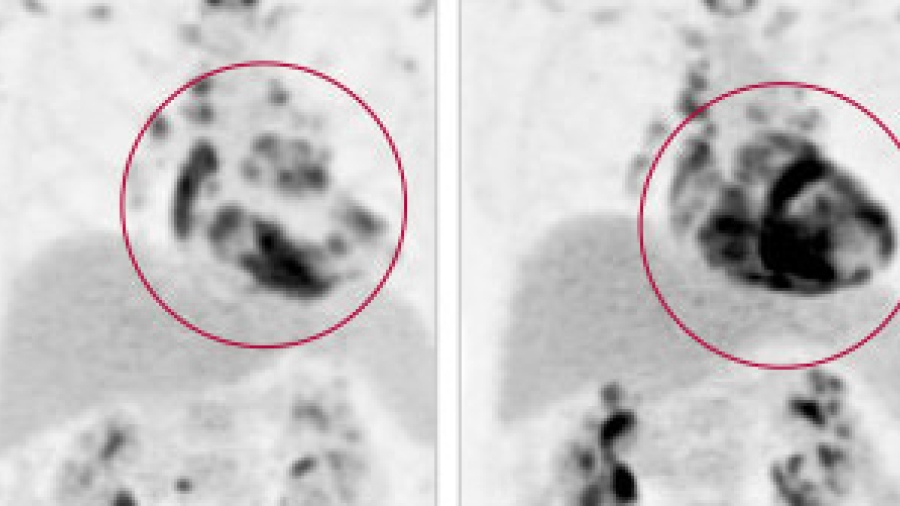

PET scan of cardiac sarcoidosis

June 26, 2017

Making the Diagnosis: Why Cardiac Sarcoidosis Should Be on Cardiologists’ Radar